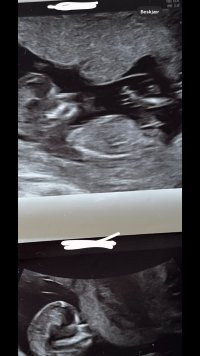

Her er det ikke noen kjønnsorgan som er synlig dessverre :/Er det tissen hans/hennes vi ser her? Jentetiss eller guttetiss, tror dere??

Ikke her heller sikkert? Mente kanskje det under beina kanskje kunne være kjønnsorganet, men er sikker noe annet ja..Her er det ikke noen kjønnsorgan som er synlig dessverre :/

Holder en knapp på jente jegIkke her heller sikkert? Mente kanskje det under beina kanskje kunne være kjønnsorganet, men er sikker noe annet ja..

Jeg tipper jente, uten å egentlig ha veldig peilingNoen som vil gjette på disseSynes det er så vanskelig og vite siden begge bildene er så forskjellig, så vet ikke om det ene bildet er nuben som peker sykt opp, eller om det er den lille andre greia under. Chat gtp sa jente på begge, men vet jo at den ikke er til å stole på, så jeg tror kanskje noe annet

Den der er vanskeligEr det tissen hans/hennes vi ser her? Jentetiss eller guttetiss, tror dere??

Ikke noe som peker åpenbart opp hvertfall, uten at jeg har peiling. Så vi sier jente, hehe Det er det jeg tror selv ogsåDen der er vanskelig

Ikke noe som peker åpenbart opp hvertfall, uten at jeg har peiling. Så vi sier jente, hehe